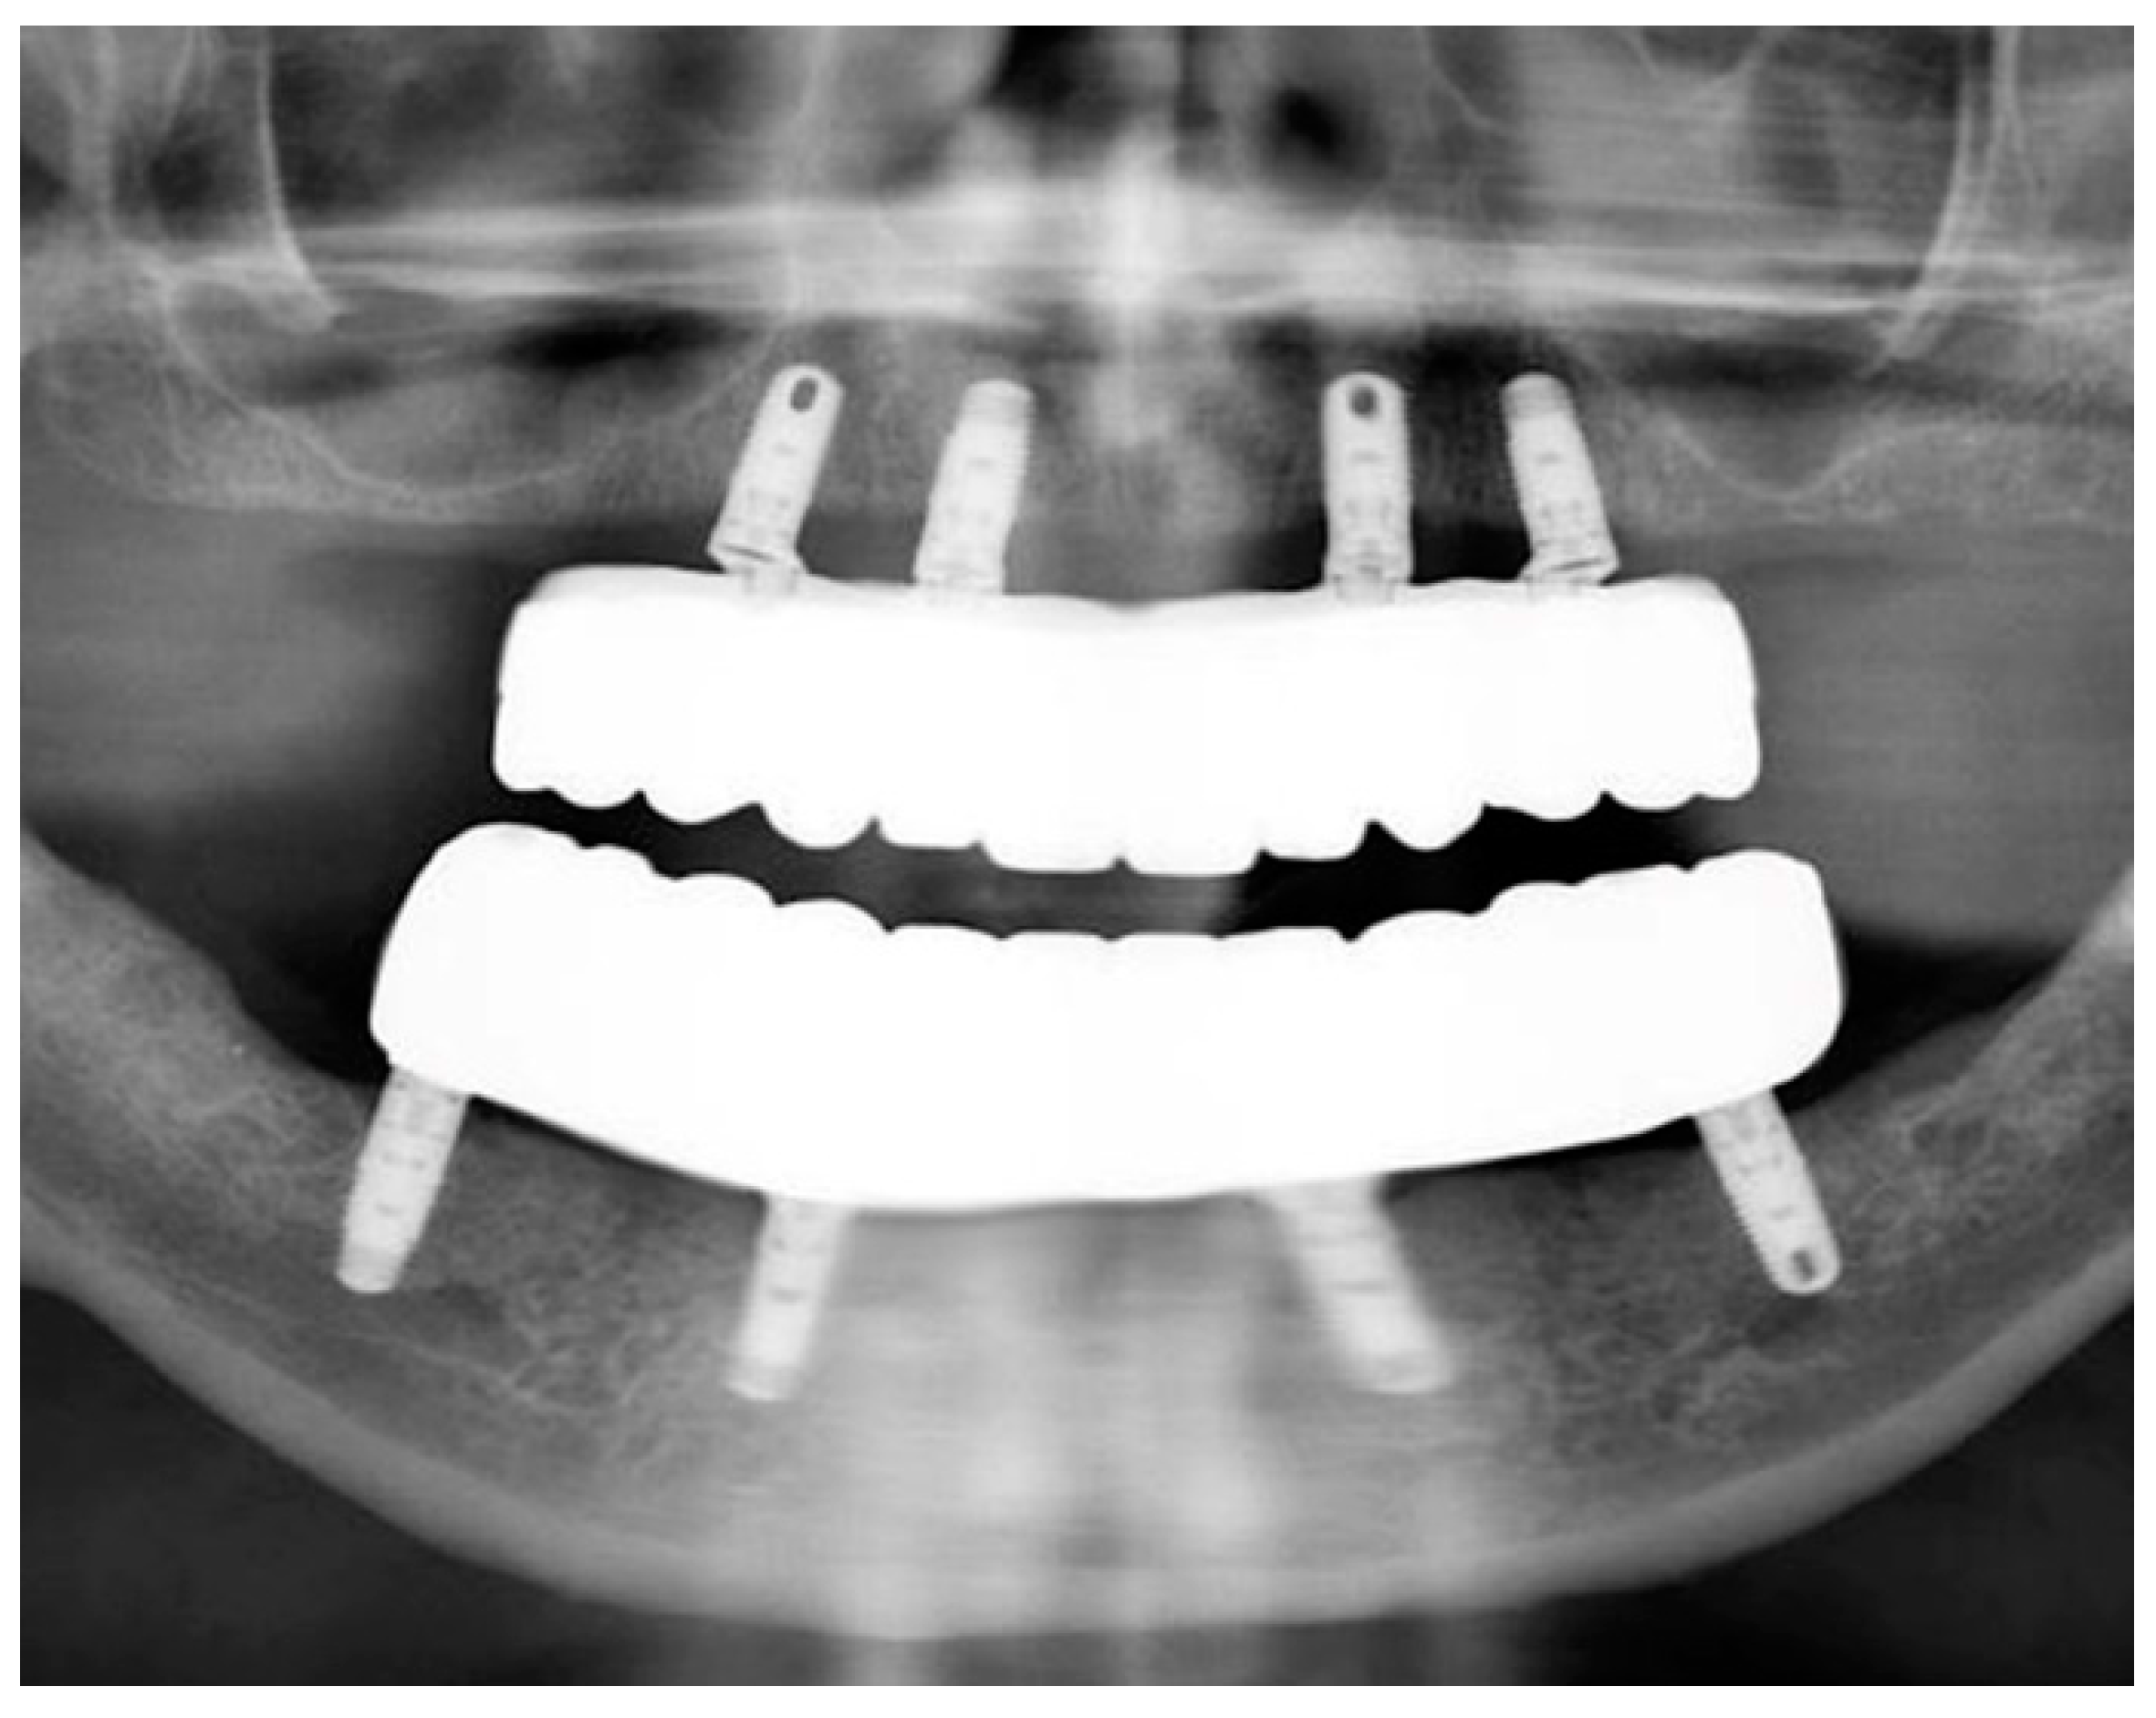

The passivity and accuracy of the fit were assessed clinically and radiographically (Figure 10), and the abutment screws were tightened to the recommended manufacturer’s recommended torque values.

Figure 10.

Panoramic radiograph of maxillary and mandibular prostheses taken at the time of delivery.